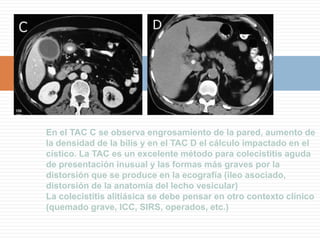

En el TAC C se observa engrosamiento de la pared, aumento de la densidad de la bilis y en el TAC D el cálculo impactado en el cístico. La TAC es un excelente método para colecistitis aguda de presentación inusual y las formas más graves por la distorsión que se produce en la ecografía (ileo asociado, distorsión de la anatomía del lecho vesicular)La colecistitis alitiásica se debe pensar en otro contexto clínico (quemado grave, ICC, SIRS, operados, etc.)

En el TACC se observa engrosamiento de la pared, aumento de la densidad de la bilis y en el TAC D el cálculo impactado en el cístico. La TAC es un excelente método para colecistitis aguda de presentación inusual y las formas más graves por la distorsión que se produce en la ecografía (ileo asociado, distorsión de la anatomía del lecho vesicular)La colecistitis alitiásica se debe pensar en otro contexto clínico (quemado grave, ICC, SIRS, operados, etc.)